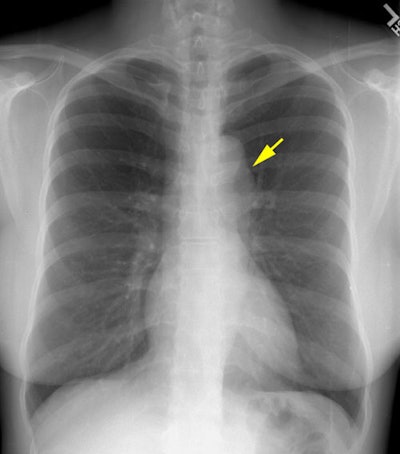

The 35 year old female patient in this case presented for routine chest radiographic evaluation.The plain film chest radiograph demonstrates a focal convexity to the descending aorta just distal to the aortic arch (yellow arrow). There is some prominence noted to the descending aorta just beyond the arch on the lateral view.